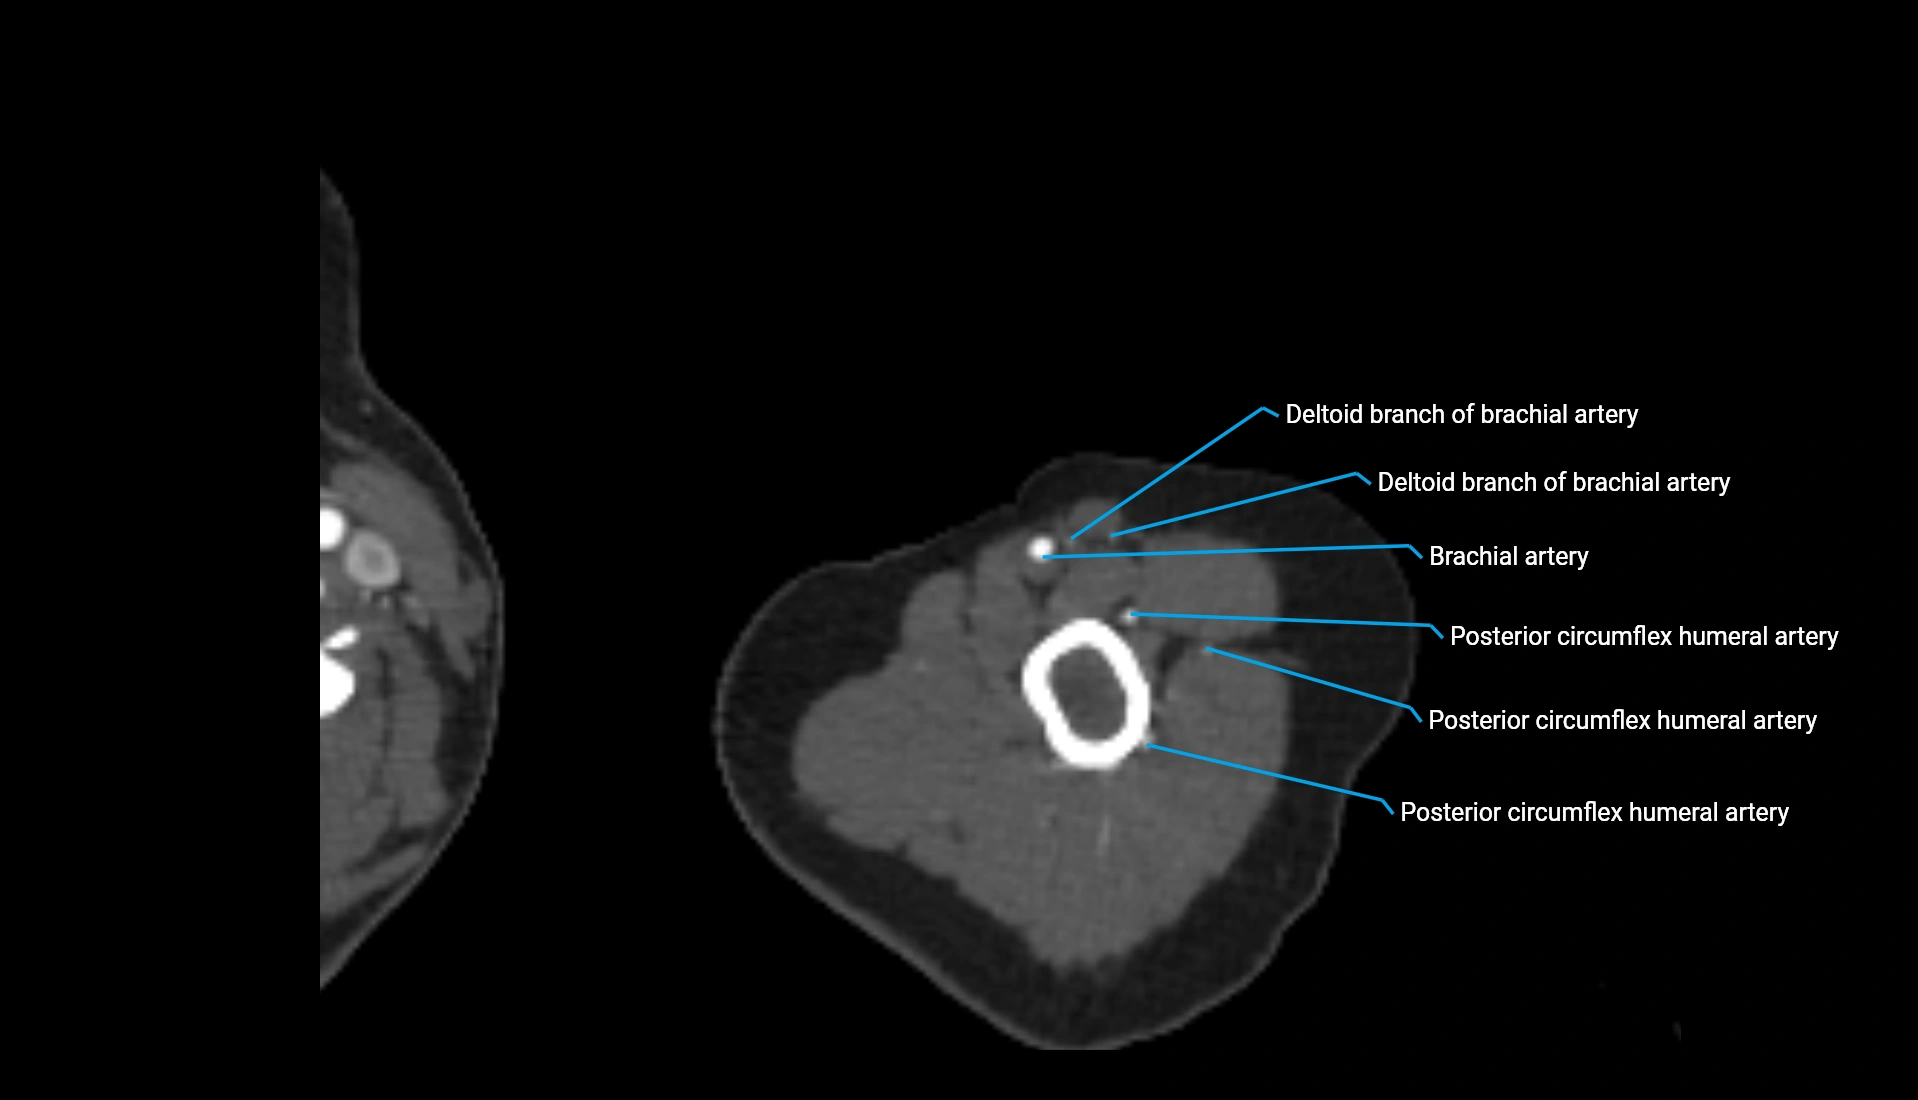

CT Appearance

Non-Contrast CT:

• Cortex: High-density, sharply defined

• Subchondral bone: Dense cancellous matrix

• Articular surface: Smooth concave contour articulating with the capitellum

• Excellent for evaluating bone integrity, alignment, and subtle fractures

Post-Contrast CT:

• Bone: No enhancement

• Joint capsule and synovium: Mild enhancement outlining the joint

• Improves contrast between soft tissues and bony margins

• Useful in detecting subtle joint abnormalities or postoperative changes